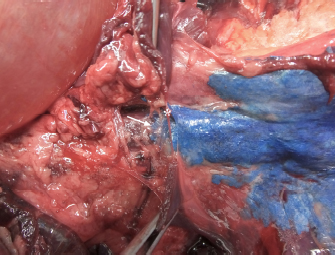

Fig. 7. NMB and ioversol longitudinal ipsilateral thoracic paravertebral spread in a dog cadaver. Ventral view.

Although with some minor intra- and inter-specific differences, a positive air-LOR test was associated with longitudinal spread along the extrapleural compartment of the TPVS in 100% of the animals. In dog cadavers, the median injected volume (ml kg−1) of the mixture was 0.6 ml (0.22–1.25). The lateral thoracic radiographs showed multi-segmental spread in 100% of the subjects, with a median of 4.5 (2–10) vertebrae and a distribution of 2.5 (0–7) vertebra cranial and 1.0 (0–3) vertebra caudal to the injection level. A longitudinal spread pattern was noted on all radiographs, mixed with a cloudy pattern in 11/14 (78%) images and with an intercostal pattern at the level of the ninth intercostal space in 1/14 (7%) image (Fig. 6). Necropsy revealed multi-segmental ipsilateral longitudinal spread in 100% of the subjects (Fig. 7). The median stained intercostal spaces were 6.5 (4–11), with 5 or more spaces stained in 78%, whereas contralateral longitudinal spread was detected in 9/14 (64.3%) spaces, with a median of 2.5 (0–6) (Fig. 8). The median cranial versus caudal spread ipsilateral and contralateral to the injection site was 3 (1–7) versus 2 (0–3) and 0 (0–4) versus 1 (0–2) space, respectively. Distributions of NMB and ioversol after each mixture injection are shown in Figure 9. The only statistically significant correlation was between the radiographical and the necroscopic assessment of the longitudinal spread in the dog cadavers ( p=0.0028).